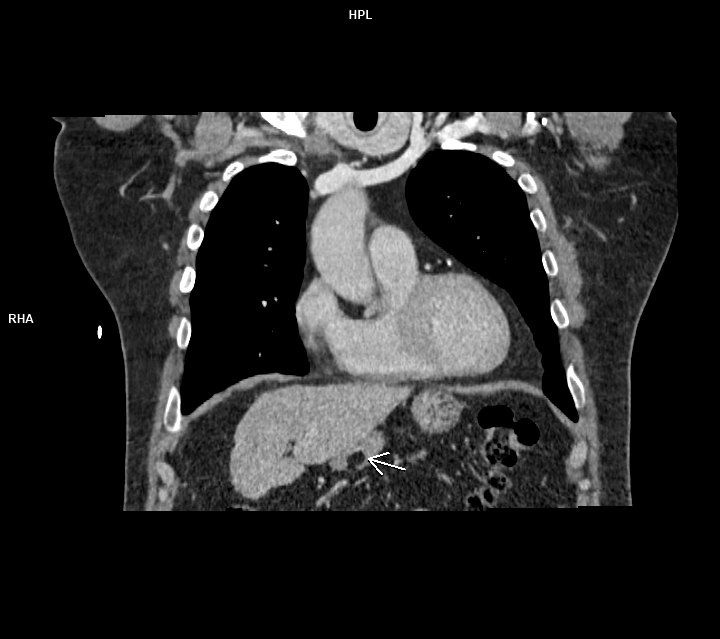

Figura 3: coronal CT postcontrast timp venos

Discuţie caz nr 89: lipomul de perete gastric este o tumoră benignă rară de origine mezenchimală ce este, de obicei, descoperire întâmplătoare sub formă unei arii circumscrise cu densități grăsoase ce sunt asimptomatice cand au dimensiuni mici. Sunt de obicei formate din celule grăsoase mature înconjurate de capsulă. Ca și în cazul nostru, sunt întâlnite mai frecvent în antrul gastric. Sunt diagnosticate prin CT deoarece au densități cuprinse între -70 și -120UH .

DE LUAT ACASĂ!!! Lipoamele gastrice sunt cel mai bine diagnosticate prin CT. Septurile fine ale țesuturilor moi probabil indică ulcerații sau modificări post-biopsie; liposarcomul gastric este extrem de rar. IRM-ul poate fi utilizat la copii sau la pacienții radiosensibili; tehnicile CT cu doze mici sunt de asemenea suficiente pentru diagnostic. Lipoamele mai mici de 3 cm sunt asimptomatice. Lipoamele simptomatice mai mari pot fi rezecate endoscopic dacă baza lor este mai mică de 2 cm; rezecția leziunilor cu baze mai largi a fost în mod tradițional retrogradată la rezecția chirurgicală, deși tehnici endoscopice mai noi s-au dovedit eficiente.